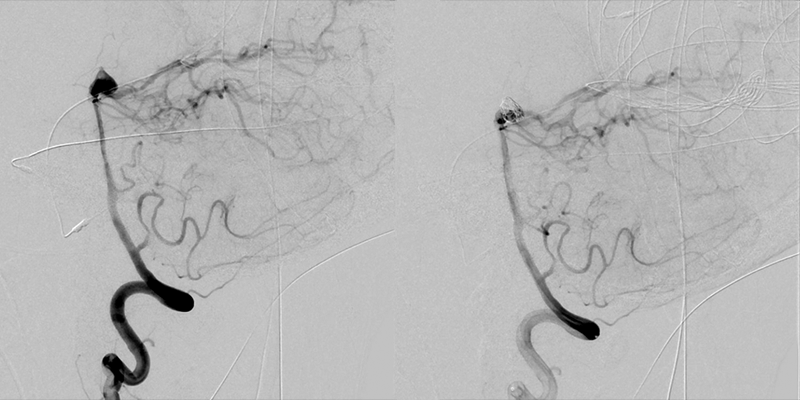

General anesthesia is maintained for the procedure. A basilar tip aneurysm, measuring 8mm x 4mm x 7mm, as well as a right ophthalmic artery aneurysm, measuring 1.2mm x 1mm x 1.5mm, are identified. The basilar tip aneurysm is successfully coiled. The common femoral arteriotomy is closed with a closure device. The patient is kept intubated and sedated and is brought up to the NCCU post-procedurally.

DCA before/after

(Before and After)